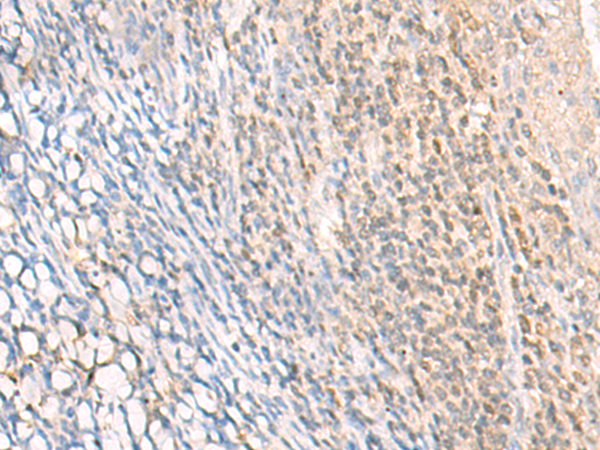

IHC positive control: |

Human cervical cancer and Human tonsil |

IHC Recommend dilution: |

30-150 |